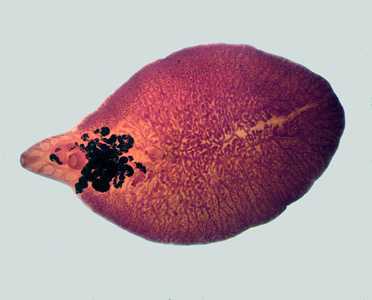

A 35-year-old man from Nepal presented at a hospital with recurring cholangitis; the patient had been experiencing symptoms for the previous six months. An MRI revealed two lesions in the liver, measuring approximately 5 centimeters long by 2 centimeters wide. Both lesions had cystic as well as solid components. An endoscopic retrograde cholangiopancreatography (ERCP) was also performed in the common bile duct, revealing flat leaf-shaped objects (Figures A-B). The objects were removed and collected in 10% formalin; they measured on average two centimeters in length (Figure C). One of the specimens was sent to a reference laboratory for identification, where it was stained with carmine (Figure D). What is your diagnosis? Based on what criteria?

Figure A

Figure B